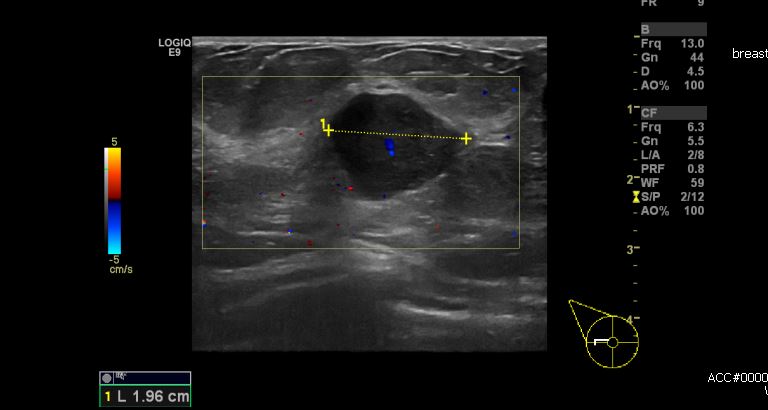

상기환자 건강검진상 이상소견으로 내원하신 70대 여성분으로 우측 9시 방향에 위치한

혹 조직검사 시행하였으며 유듀형상피내암 진단 되었습니다.